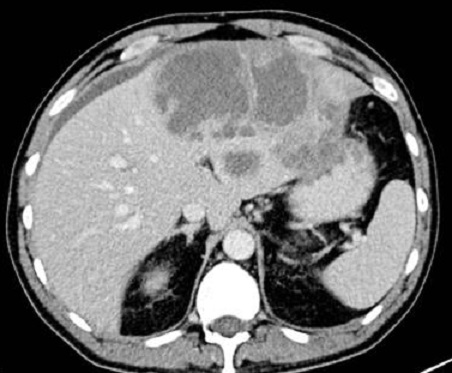

Image en cible

d'une abces du foie droit . CoupeTDM axiale 90

seconde apres injection de contrast intraveineuse .

Aspect lesionnel est un contour hyperdense et un

centre hypodense pseudokystique " double target sign

" |

Aspect lesionnel

de masse ovalaire

, hypodensite a bord bien definies , rehausse

peripherique apers injection de contrast

intraveineuse . Image de la

présence de gaz dans ce

abces peut en orienter d’un abcès à pyogène . Ce

signe n’est présent que dans 19 % des cas

. |